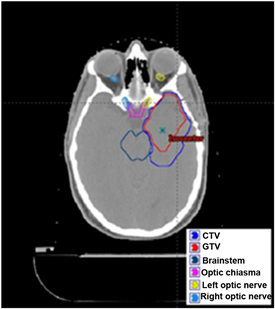

Figure 1 shows the outlining of the target volumes and organs at risk (OARs) for the brain cancer treatment plan on a computed tomography slice. The prescribed doses were 5700 and 5000 cGy (RBE) (RBE = relative biological effectiveness) to the gross tumor volume (GTV) and clinical target volume (CTV), respectively, in 30 fractions. The maximum dose constraint for the chiasma, both optic nerves,

Figure 1. Contours of the GTV, CTV, and organs at risk (brainstem, optic chiasm, left optic nerve, and right optic nerve) have been drawn on this CT slice for the actual brain cancer IMPT plan.

and the brainstem was 5400 cGy (RBE). The optic chiasma, left optic nerve, and brainstem were at the edge of the target volumes.